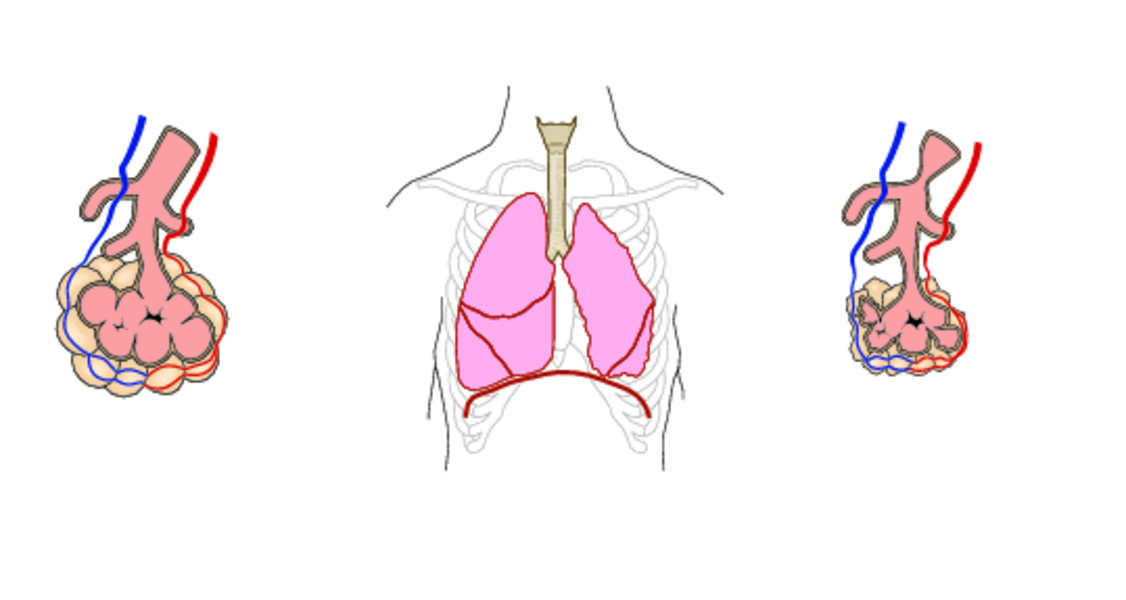

- если поражен лишь 1 ацинус (структурная единицы легких, которая включает в себя дистальный (наиболее удаленный) бронх с гроздьями альвеол), ателектаз называют ацинозным;

- в случае поражения дольки – дольковым;

- при поражении сегмента – сегментарным;

- одной доли легкого – долевым;

- всего легкого – тотальным.